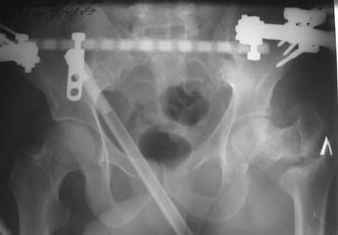

Уважаемые коллеги! Нужен совет.Больной Х., 21 год, ДЗ: ложный сустав вертельной области правого бедра.

Травма 8 мес. назад, ДТП, получил закрытый межвертельный перелом правого бедра. Лечился в городской больнице одного из городов-спутников г. Караганды скелетным вытяжением в течение 3 недель, затем кокситной гипсовой повязкой 2 мес. В настоящее время имеется укорочение конечности на 7 см, умеренная боль в вертельной области; ходит без костылей, полностью нагружая больную конечность, при нагрузке отмечается смещение дистального отломка проксимально примерно на 1,0 см.; объем движений в коленном суставе сохранен; при пальпации отломков боли нет, умеренная патологическая подвижность. Планируем внеочаговый остеосинтез спице-стержневым аппаратом, дистракция до восстановления длины бедра, вторым этапом остеосинтез стержнем Гамма. Есть надежда, что на дистракции пойдет сращение и у больного хватит терпения завершить лечение в аппарате.

Снимки были в приложенном pdf файле. Сейчас они выложены отдельно, вверху исходного сообщения. Если их не видно, перезагрузите страничку.

В приложении пример пациента, близкого по картине к тому, что представил Виктор (варус и смещение периферического отломка на поперечник кзади). Сделали как раз то, что Виктор исходно намеревался - аппаратная коррекция и затем гамма.

Виктор! Судя по снимкам,укорочение не более 2-3 см (даже линия Шентона сохранена). При таком укорочении дистракционный остеосинтез аппаратом внешней фиксации на конкретном сегменте,действительно представляется агрессивным.Может быть,как предлагает D.Kuldjanov,ограничиться предоперационным скелетным вытяжением и после рентгенконтроля использовать Blade Plate или Гамму с губчатой аутопластикой.Возможна миотомия приводящих мышц.Смещение не столь велико,чтобы его форсированное устранение грозило неврологическими осложнениями.Даже остаточное укорочение в пределах 1см вряд-ли усложнит операцию и существенно повлияет на исход.Учитывая статус клиники,для пациента не менее важны комфортность в послеоперационном периоде,возможность полноценно жить и работать в период реабилитации, максимальное снижение вероятности послеоперационных осложнений.А этим условиям аппарат Илизарова не отвечает.

Если судить по снимкам, то укорочение кажеться не критическим, но обьективно и на 3D - укорочение на 6-7 см.